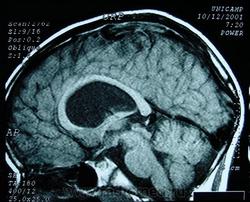

Шизенцефалия. Шизэнцефалия, щель между желудочками и субарахноидальным пространством, Полимикрогирия, агенезия прозрачной перегородки. Отдел патологии, школа медицинских наук. Государственного Университета Кампинас (UNICAMP). Кампинас, Сан-Паулу, Бразилия. Втр, 31/01/2012 - 10:07 #1 unre_ALL Не на сайте Был на сайте: 8 лет 3 месяцев назад Зарегистрирован: 15.09.2010 - 14:52 Публикации: 187 Да... врожденное состояние. Помню на одном форуме пациент выложил похожее, спросил что это? Случайно увидел, написал такой диагноз. На что мне доктор, хозяин портала, авторитетно отписал: Такого диагноза нет и не было! Шизоферния есть, а шизэнцефалии нету! ------------------------------------------------------------------------------------------------- Я получил счет от хирургов. Теперь мне понятно, почему эти парни работают в масках. Сб, 28/04/2012 - 23:31 #2 Катенёв Валенти... Не на сайте Был на сайте: 7 лет 4 месяцев назад Зарегистрирован: 22.03.2008 - 22:15 Публикации: 54876 ШизенцефалияПриложения: Сб, 14/07/2012 - 18:44 #3 Катенёв Валенти... Не на сайте Был на сайте: 7 лет 4 месяцев назад Зарегистрирован: 22.03.2008 - 22:15 Публикации: 54876 Шизенцефалия.Приложения: Вс, 09/09/2012 - 10:20 #4 Катенёв Валенти... Не на сайте Был на сайте: 7 лет 4 месяцев назад Зарегистрирован: 22.03.2008 - 22:15 Публикации: 54876 Шизенцефалия.Приложения: Пнд, 24/09/2012 - 19:01 #5 Катенёв Валенти... Не на сайте Был на сайте: 7 лет 4 месяцев назад Зарегистрирован: 22.03.2008 - 22:15 Публикации: 54876 http://www.ajronline.org/content/150/6/1391.full.pdf+html Приложения: Чт, 23/07/2015 - 08:07 #6 Катенёв Валенти... Не на сайте Был на сайте: 7 лет 4 месяцев назад Зарегистрирован: 22.03.2008 - 22:15 Публикации: 54876 http://radiomed.ru/cases/kt-gm-otkrytaya-shizencefaliya Сб, 29/10/2016 - 13:38 #7 Катенёв Валенти... Не на сайте Был на сайте: 7 лет 4 месяцев назад Зарегистрирован: 22.03.2008 - 22:15 Публикации: 54876 Отдел патологии, школа медицинских наук, Государственного Университета Кампинас (UNICAMP). Кампинас, Сан-Паулу, Бразилия. Приложения:

Шизенцефалия

Отдел патологии, школа медицинских наук,

Государственного Университета Кампинас (UNICAMP).

Кампинас, Сан-Паулу, Бразилия.